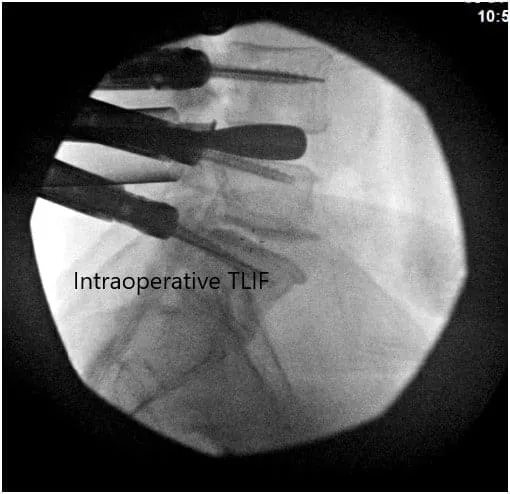

Intraoperative Fluoroscopic Images.

All needles were placed under fluoroscopic imaging and once we were satisfied with the positioning, we then evaluated his nerve monitoring and found there to be no changes within any of the needle positions. We then proceeded to place a guidewire into the vertebral body and then removed the Jamshidi needle.

We then secured the guidewires onto the edge of the patient’s bed and turned our attention towards performing the decompression and interbody fusion procedures. We then used a microscope to began our decompression at the L4-L5 region.

We first began with the left side and placed a size #60 mm length rod into position. We then secured it and ensured that there was an adequate amount of lumbar lordosis. We then also secured the right side rod with a similar length into position.

We then obtained final fluoroscopic images and were completely satisfied with our fixation and alignment. We then washed out the wounds with normal saline and vancomycin instilled into the wound. We proceeded to close the layers with a size #2 Vicryl sutures for the fascia layer followed by size #2-0 Vicryl suture for the subcutaneous skin and a running #4-0 Monocryl suture for the subcuticular layer.